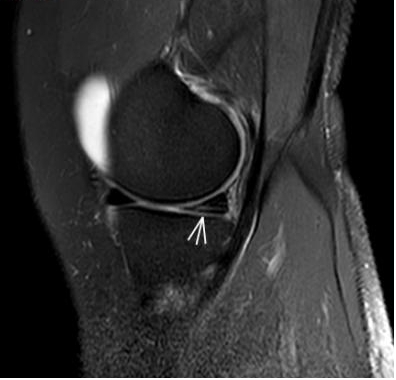

2. 運動后“打軟腿”——韌帶的“斷弦危機(jī)”

場景:打球急停后膝蓋不穩(wěn),走路像“踩棉花”

MRI偵查:揪出前交叉韌帶斷裂(呈“波浪狀”或連續(xù)性中斷)、內(nèi)側(cè)副韌帶損傷,防止關(guān)節(jié)“脫軌”

(內(nèi)側(cè)副韌帶損傷)